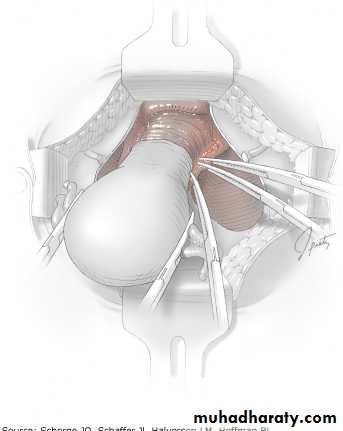

What is this operation?

Enumerate the advantages and the disadvantages of this operation?What is this drug?

-what is the name of this operation?-Mention 4 indications for it.-mention 3 complications.